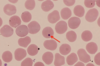

Red blood cells

Ca. 7 µm in diameter. Most numerous type of cell in blood. One microlitre of blood contains ca. 5 million cells. Essential for transport of CO2 and O2 around the body.

‘Born’ and mature in BM. When they mature, they make Hg. Eventually around 90% of the dry weight of the cell is made up of this protein. The nucleus is lost from the cell, phagocytosed by macrophages, and the DNA broken down. They can then enter the circulation.

Live for about 120 days. However, the iron in Hg is extracted from the erythrocytes by the liver and spleen, and the remaining heme is excreted by the liver as bile pigments.

Around 3 million RBCs die and are scavenged by the liver each second.

RBCs and platelets